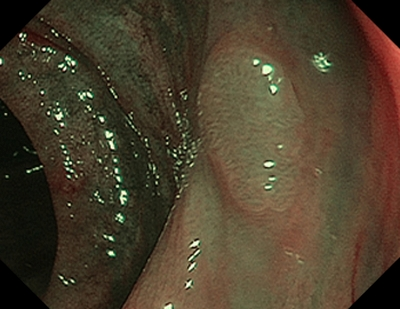

1 тип — характерний для гіперпластичного поліпа

Судини: світліші або схожі на навколишні

Поверхня: круговий візерунок з дрібними крапками — візерунок із темнішою ділянкою в центрі, оточений світлішою слизовою оболонкою